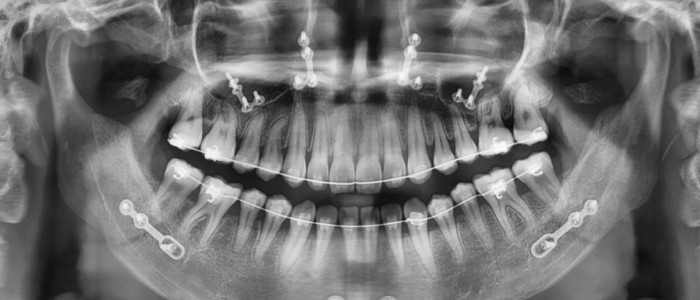

CBCT Scan

Teeth 1

View attachment 4444394

View attachment 4444397

Dental Imaging X-Ray's